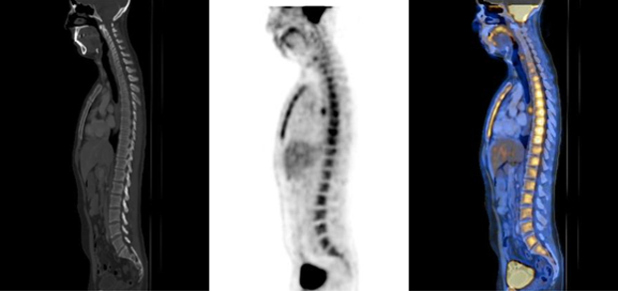

La grasa parda representa un hallazgo fisiológico que se observa con cierta frecuencia, distribuyéndose de forma relativamente simétrica y predominando en la región cervical, supraclavicular, dorsal y paravertebral (fig. 1).